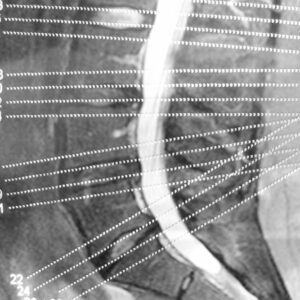

A brief overview of degenerative disc and joint disease

When you mention the term degenerative disease, it refers to the gradual deterioration of the body tissues or cells over the years due to the natural aging process. As we age, our spine starts giving in to the stress of providing flexibility and support to our back. The components of the spine start deteriorating slowly, and you will experience back pain and stiffness in the spine.